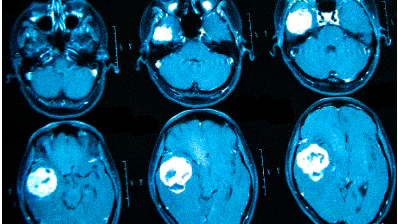

МРТ при головных болях (в трех проекциях): специальная программа выстраивает объемные изображения полученных срезов, что позволяет увидеть даже мельчайшие изменения и отдифференцировать патологию от нормы

Причин головной боли множество, и их не всегда возможно определить без помощи современных способов визуализации. Цефалгию вызывают: повышенное внутричерепное давление, сосудистые мальформации, опухолевые процессы, постравматические осложнения. Какую МРТ делать при головной боли или предпочтительней пройти КТ — зависит от предполагаемого характера патологии. Все методы являются взаимодополняющими, но что лучше в конкретном случае, выбирает врач с учетом жалоб, показаний и противопоказаний. МРТ и КТ с контрастным усилением позволяют получить сопоставимые по качеству снимки, но при этом используют разные принципы построения изображений. Чем раньше будет найдена причина и проведено адекватное лечение, тем больше шансов на полное выздоровление.

Выделяют несколько видов магнитно-резонансной томографии головы: нативную, усиленную  контрастным препаратом и сканирование в ангиорежиме. К каждому исследованию есть свои показания, поэтому ответить на вопрос: “Какую МРТ делать при головной боли?” — не всегда возможно. Врач выбирает нужный тип диагностики, опираясь на клиническую картину. В оценке опухолевых новообразований и для определения стадийности (в том числе — метастатического распространения) используют МРТ с контрастированием. Введение препаратов на основе хелатов гадолиния позволяет рассмотреть даже небольшие опухоли в труднодоступных местах, поэтому магнитное сканирование с усилением с успехом применяют, если прочие способы визуализации показали неоднозначные результаты. При подозрении на сосудистое заболевание головного мозга оптимальным выбором будет проведение сканирования в ангиорежиме.